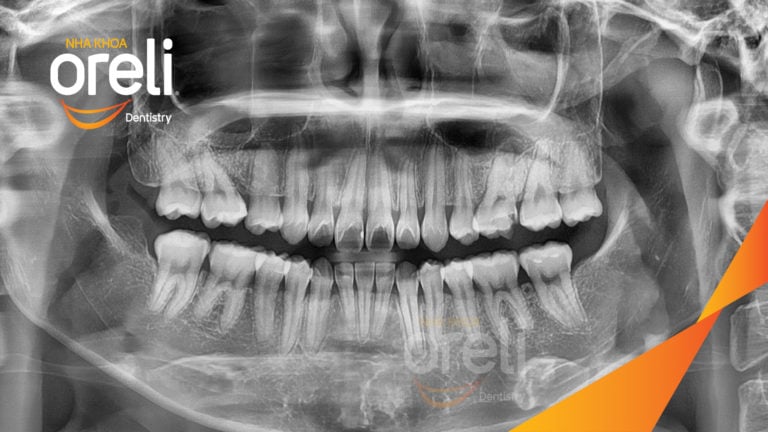

Ca niềng răng đặc biệt: kéo răng 7, 8 thay thế 3 răng 6 bị hư tại Oreli Niềng răngDi gần răng 7 8 Xem thêm